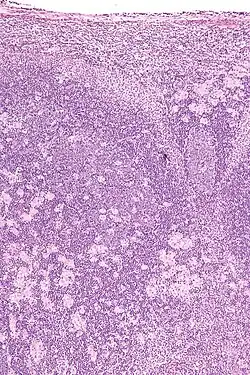

Lymph nodes affected by Toxoplasma have characteristic changes, including poorly demarcated reactive germinal centers, clusters of monocytoid B cells, and scattered epithelioid histiocytes.

Micrograph of a lymph node showing the characteristic changes of toxoplasmosis (scattered epithelioid histiocytes (pale cells), monocytoid cells (top-center of image), large germinal centers (left of image)) H&E stain